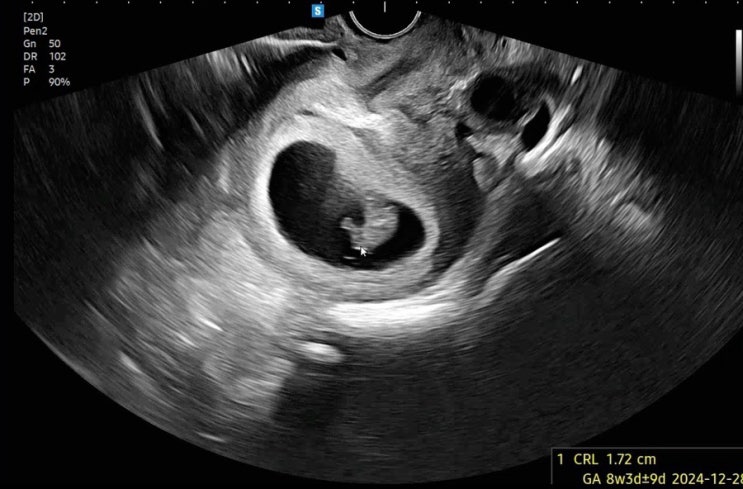

임신 7,8주차 / 여전한 입덧과 환도선다 그리고 태아보험 가입까지 완료

7주차 증상 - 입덧 시간이 지날수록 점점 더 심해지는 입덧 ㅜㅜ 다행히(?) 토덧은 아니고 울렁덧이다 5/17...